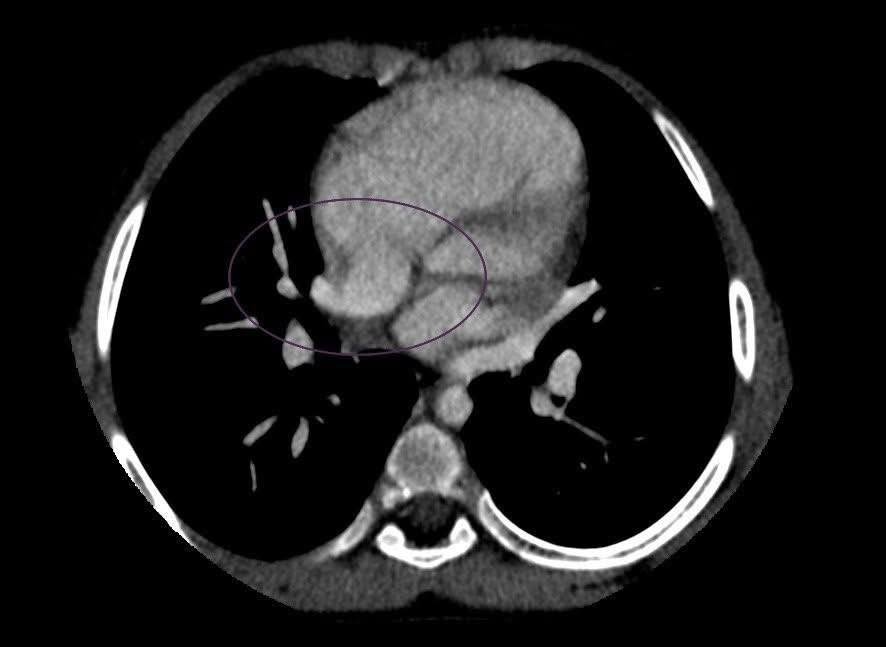

У Чернівцях семирічній дитині вперше зробили КТ серця прямо в обласній лікарні

Дитині з родини переселенців діагностували ваду серця і готують до хірургічного лікування

До Чернівців спеціально приїхали фахівці Інституту серцево-судинної хірургії імені Миколи Амосова. Вони підтвердили підозру на ваду серця. Для точнішого діагнозу вирішили провести КТ серця з контрастуванням — і зробили це просто в обласній дитячій лікарні завдяки наявному сучасному обладнанню.

До цього дітей з такими підозрами направляли на обстеження до Києва. Тепер КТ серця можна зробити на місці, що особливо важливо у випадках, коли стан дитини не дозволяє безпечно її транспортувати. За результатами обстеження лікарі прийняли попереднє рішення про хірургічне лікування семирічного пацієнта.